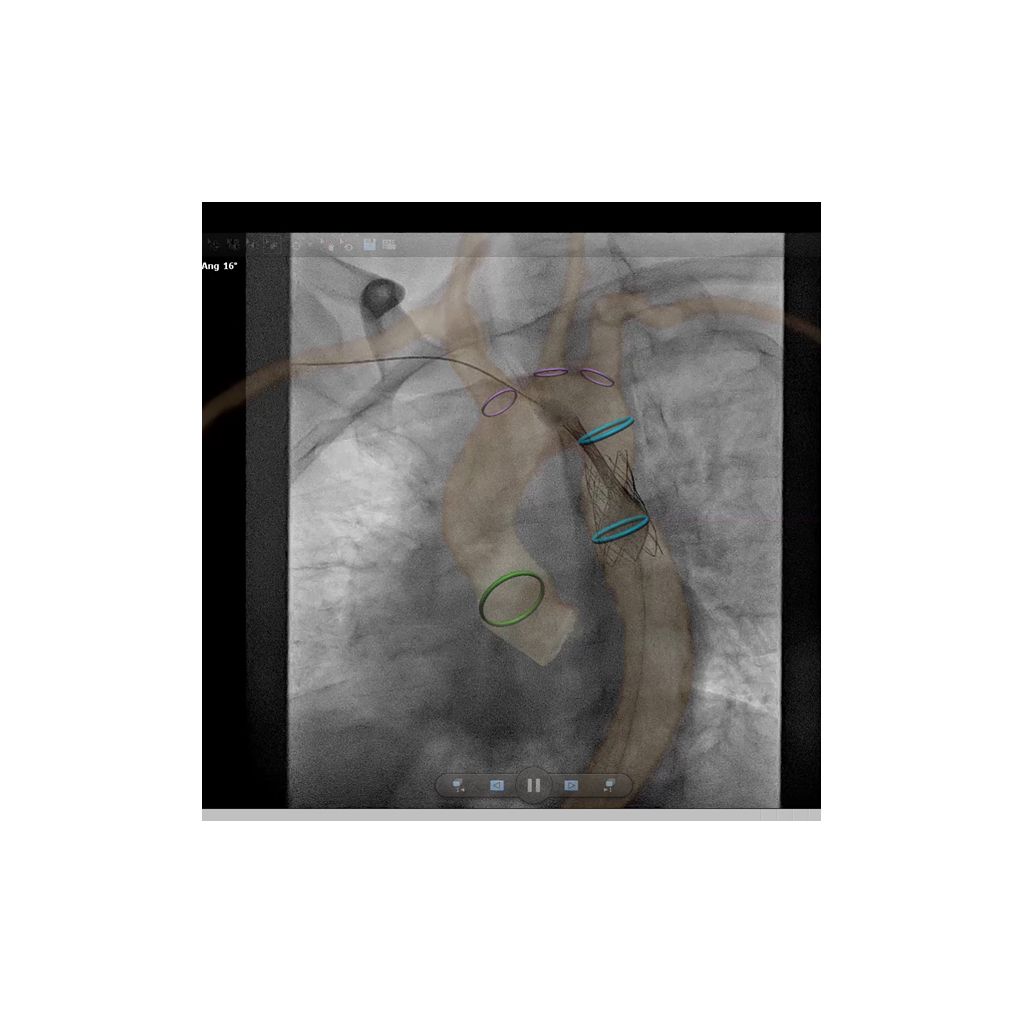

Know your path in advance with 3D image fusion technology for endovascular procedures. VesselNavigator allows you to reuse 3D vascular anatomical information from existing CTA and MRA datasets as a 3D roadmap overlay on a live X-ray image. With its excellent visualization, the VesselNavigator provides an intuitive and continuous 3D roadmap to guide you through vasculature during the entire procedure.

Live X-ray image